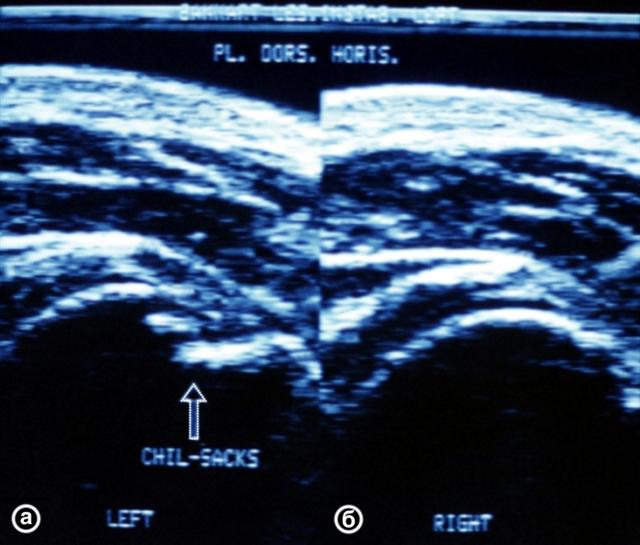

Рис. 20. Ультрасонограммы плечевых суставов (задний горизонтальный срез) при импрессионном переломе головки левой плечевой кости (а) и в норме (б): контур головки плечевой кости ступенеобразно деформирован в месте импрессии (указано стрелкой).